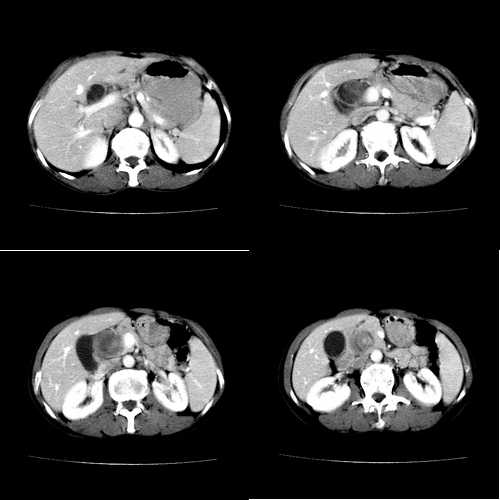

患者 女 60岁,曾多年胆结石及胆管结石,今行ct复查,非常经典.现上传,请讨论.

典型的胆总管铸型结石。

支持胆总管结石。胆囊增大受压,肝内胆管及胰腺管无明显扩张。很有意思的病例,能有冠、矢状重建图像观察就更好了。

相当漂亮的“总胆管(铸型)结石”。多谢楼主!

胆总管内多层同心圆样结石,确属精典,谢谢卜一老师!